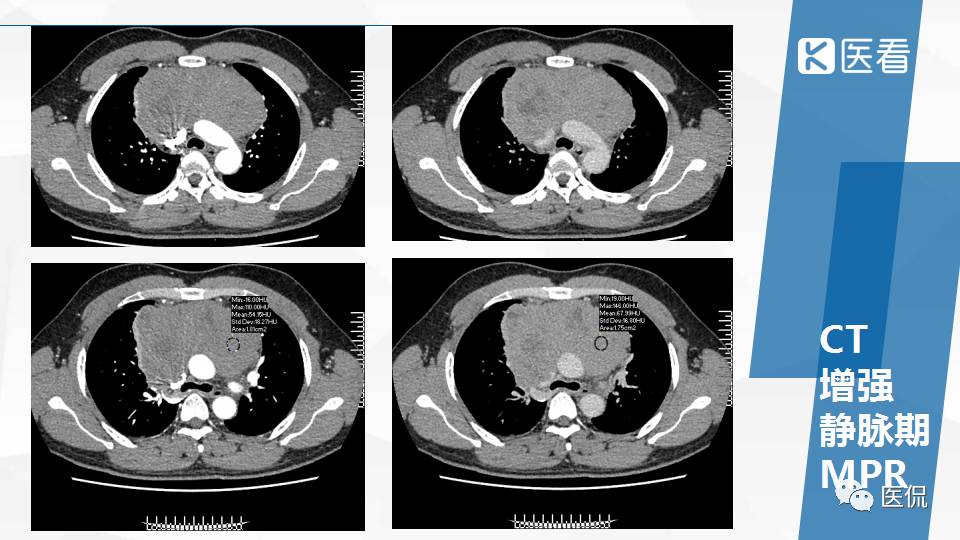

纵隔精原细胞瘤案例 (精原细胞瘤影像表现与鉴别诊断)

精原细胞瘤ct影像,精原细胞瘤影像特征